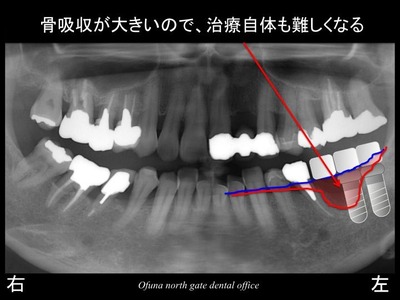

いつものように 骨吸収の状態を分かりやすくするために

骨吸収の状態を線で書いたのが以下のレントゲンになります。

青線が骨吸収を起こすの骨の位置です。

赤線は、現在の骨の位置です。

かなりの骨吸収が起こっているのが分かるかと思います。

骨吸収が大きく起こっているのでインプラント治療自体が難しくなります。